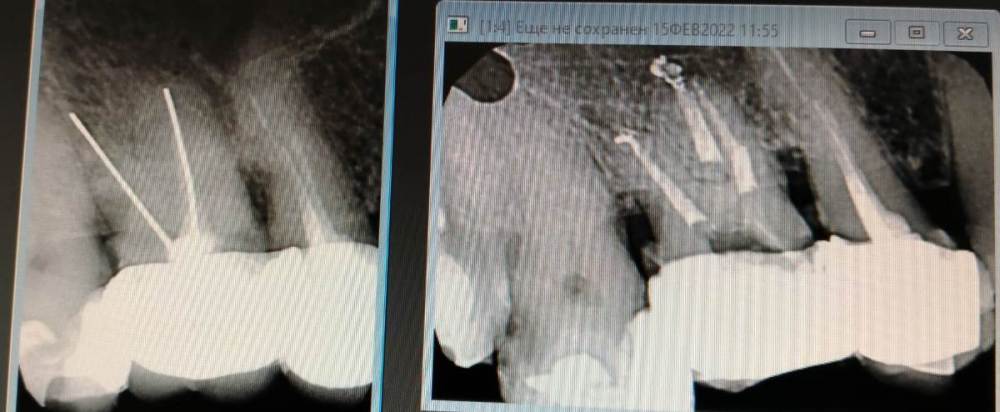

Ico Опубликовано 7 октября, 2022 Автор Поделиться Опубликовано 7 октября, 2022 В первом кейсе все стандартно,просто не каждый день такие антенны попадаются.Во втором 3 изгиба,но их хорошо в ручном режиме берут патфайлы, апексы все соединяются в нижней трети.Третий случай - ретрит со ступенькой был,тут пре рейс 30.06,тоже патфайлы + профайлы 02 конуса,далее шейпинг S1.На четвертом снимке телега не моя,направили помочь.За 1ч15м удалось извлечь фрагмент ,сначала байпас,потом чаком снял кривизну немного,и рядом нарезал площадку,которая позволила озвучить фрагмент сбоку,фрагмент выплыл стандартно. 2 1 2 Ссылка на комментарий